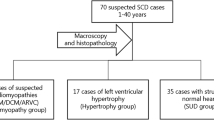

In 2012, the alpha male bonobo of the Milwaukee County Zoo’s (MCZ) large troup of 20 bonobos (Pan paniscus) died suddenly at 38 years of age. Post-mortem examination revealed gross anatomic and fine histologic features of ARVC (Fig. 1). Since only a few thousand wild bonobos now exist in the rain forest south of the Congo River and the North American captive population of 85 bonobos are progeny of only 24 wild-caught individuals, the presence of a potentially lethal genetic variant in the small gene pool of this highly endangered species could be catastrophic for species survival. Genetic studies understanding the basis of ARVC in this restricted gene pool may also provide valuable insight into the genesis of the disease in humans and other primates, leading to risk stratification and sudden death prevention.

We have exploited the remarkable nucleotide and amino acid sequence homology between humans and bonobos to perform a candidate gene sequencing analysis of the coding regions of 10 genes previously associated with human ARVC. This approach sought to identify the possible genetic defects leading to ARVC in bonobos and to develop a test that can be used on other captive bonobos. Here, we describe the methodology used to develop our sequencing panel and report the findings in the affected bonobo but not in a healthy control individual.

The primary goal of our study was to investigate the molecular basis of the seeming ARVC in a specific subject, a 38-year-old founder bonobo (Lody), who died suddenly of a histologically characterized arrhythmogenic cardiomyopathy. A definitive identification of the molecular culprit(s) would have aided in identifying individuals harboring the genetic variant(s) and attaining proper risk-stratification of Lody’s offspring, thus warranting a rigorous surveillance and appropriate medical treatment. Two of three full-sibling descendants from this founder’s mating with a founder female with progressive limb weakness of unknown etiology had early deaths, further supporting the potential inherited nature of the disease, thus adversely affecting future generations and the sustainability of this species. A secondary goal of our project was to find variants that would shed new light into the genetics of heart diseases in bonobos and develop a test panel that could be utilized by other institutions and provide a replicable, non-invasive test for all great apes to be easily screened for cardiovascular disease. This preliminary information may help identify and diagnose individuals at an earlier stage of disease progression and thus enroll them in training to participate in echocardiogram tests and other non-invasive monitoring and treatment plans. Early diagnosis is vitally important to prevention and treatment, and is especially important for the bonobo species, which is currently listed as endangered in their wild habitat (west-central Africa). Finally, in the case of the bonobo, these results will assist the Bonobo SSP in making more knowledgeable breeding recommendations for the already limited captive population.

To our knowledge, this is the first comprehensive genetic approach using targeted gene sequencing, next generation sequencing, and genome-based chromosomal microarray analysis attempting to find a genetic etiology for the ARVC presentation of a deceased alpha male bonobo from the MCZ by searching for pathogenic variants in genes previously linked to ARVC, as well as in 246 cardiovascular genes. The sequencing of other affected relatives and segregation analyses may further support the pathogenic role for each variant or support the multi-locus additive effect of a combination of variants if they co-segregate with the disease phenotype in Lody’s family members. Alternatively, the sequencing of the genes where VUSs were found or whole exome sequencing in several additional affected and unaffected captive bonobos, as well as from all four non-human primate genera may be helpful to elucidate the basis of such potentially devastating disease. We hope that through the development of this cardiovascular assessment strategy, the bonobo, as well as the other great apes, will benefit from the molecular technologies currently available and therefore be more likely to live a longer, more productive life, and be able to contribute to the breeding and preservation of their species. We have a rare opportunity to utilize the large, collaborative efforts and data banks from human studies for the benefit of our closely-related apes. Finally, findings from non-human primates may make clinical significant contributions to the overall understanding of ARVC in human subjects.